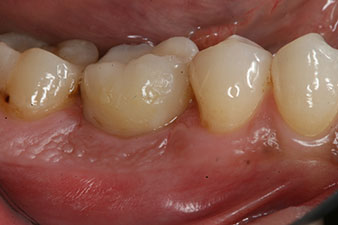

Fig. 6: Ten weeks later the gingiva former, which was screwed in place after placement of the implant, can be removed. In the linguo-buccal direction the ISQ value was virtually unchanged at 63 (measuring probe in proximity at a distance of 2-3 mm).

The implant was uncovered two months later and a gingiva former was screwed in (no picture).

After healing of the soft tissue, the implant stability was measured again before delivery of the prosthetic restoration.

Both values were virtually unchanged and were between the medium and the high range – where the lower value is always used as the reference value that determines the treatment.